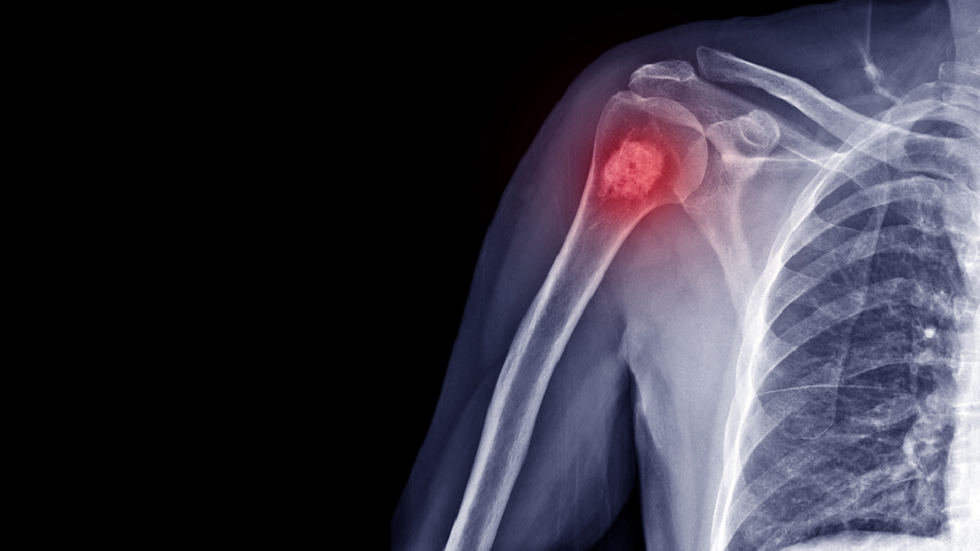

ما هي خطورة الورم العظمي؟

تشير الدكتورة سونا إيساكوفا أخصائية الأورام إلى أن الورم العظمي هو مرض حميد نادر، يتميز بتكاثر أنسجة العظام، وغالبا ما يصيب عظام الجمجمة.

علاج واعد يستهدف نوعا شائعا من سرطان العظام

ووفقا لها، يشخص هذا المرض عادة بعد سن الأربعين لدى الرجال والنساء على حد سواء.

وتقول: "لم تحدد إلى الآن أسباب أورام العظام، ولكن يفترض وجود صلة بينها وبين الصدمة أو العملية المعدية. ونادرا تحدث حالات متعددة من هذه التكوينات مع المرض الوراثي-متلازمة غاردنر. ولا تظهر أعراض الورم العظمي عادة، ويكتشف عن طريق الصدفة. ويكفي في أغلب الحالات إجراء فحص بالأشعة المقطعية لتشخيص الحالة، ولكن في بعض الأحيان إذا كان يبدو غير طبيعي يتم إجراء ثقب لتقييم خلايا تكوينه".

ووفقا لها، يعالج الورم العظمي فقط جراحيا عندما تكون لدى المريض شكاوى متعلقة به. ووفقا لموقع الورم قد يكون هناك صداع، ضعف حاسة الشم، ازدواجية الرؤية.

وتقول: "إذا لم تزعج أعراض الورم العظمي المريض، فلا يستأصل، لأنه حميد ولا يشكل خطرا على الصحة".

المصدر: صحيفة "إزفيستيا"